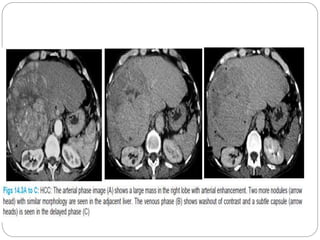

CT SCAN  3patterns:  Solitary  Multicentric  Diffuse  Large hypodense mass  Central low attenuation due to necrosis

• 23.

CT  Focal calcification- 7.5%  Majority - hypervascular  arterial phase  Heterogenous enhancement due to central necrosis  Isodense on delayed images  Angioinvasive: portal vein /IVC  Central Necrosis- Hetrogeneous +C

Arterial phase  Demonstrationof arterial branches tumour  Arterio portal shunts Arterio-portal shunt: The arterial phase CT image shows a large enhancing lesion (m) in the segments 3 and 4 of liver with contrast in the left hepatic artery (arrow) and left branch of portal vein (arrow head) suggesting arterio-portal shunting